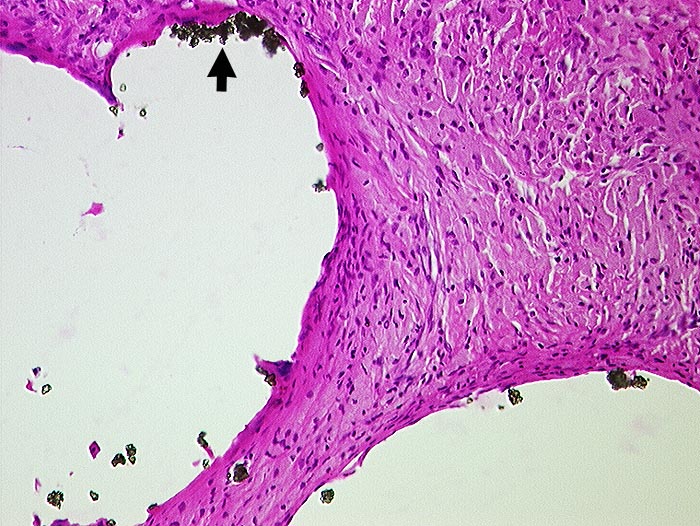

Zementabrieb

Artefakt / Fremdkörper / Pigment

Weichteile Hüfte

Weichteile

Vernarbtes geringgradig entzündlich infiltriertes Gewebe aus dem Pfannengrund. In grossen Hohlräumen liegen

►

Bariumpartikel. Der Zement ist durch die Verarbeitung herausgelöst worden.

Hüft-TP Wechsel.